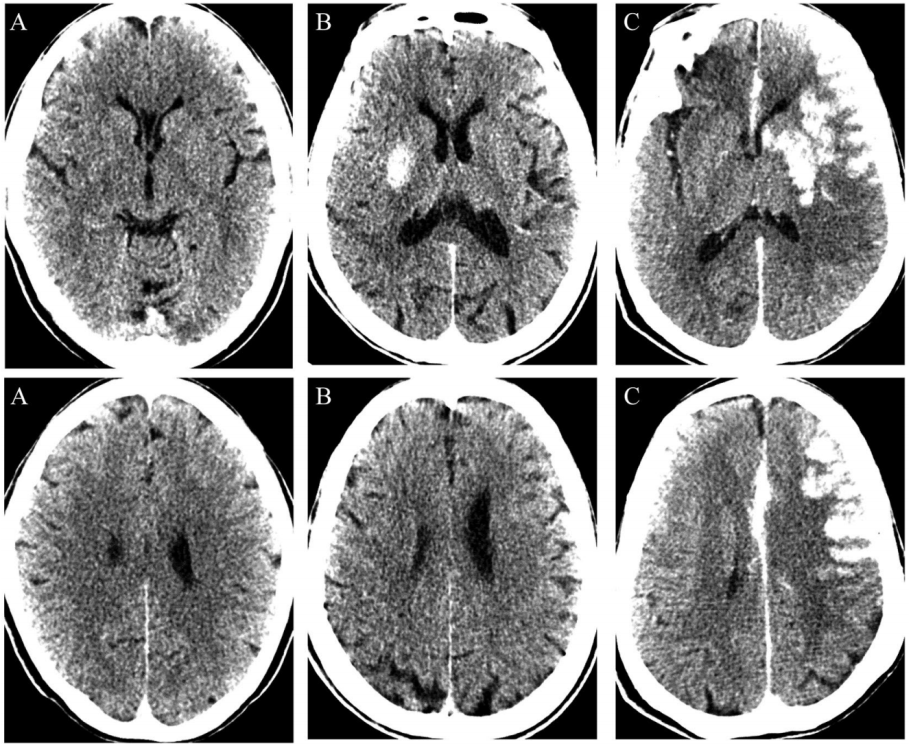

病例学习:颅骨修补术后恶性脑水肿一例

术前头颅ct显示右侧颞顶叶大面积占位病变,周围水肿明显,中线左移近

2017年2月17日术后立即复查头颅ct显示:术后额叶水肿.

术后3周ct复查,脑水肿消退,中线居中.

颅骨缺损修补术后恶性脑水肿一例丨颅脑创伤神经重症病例周刊第31期

图1颅脑ct示脑组织水肿明显,双侧基底节,顶叶,枕叶可见片状低密度影